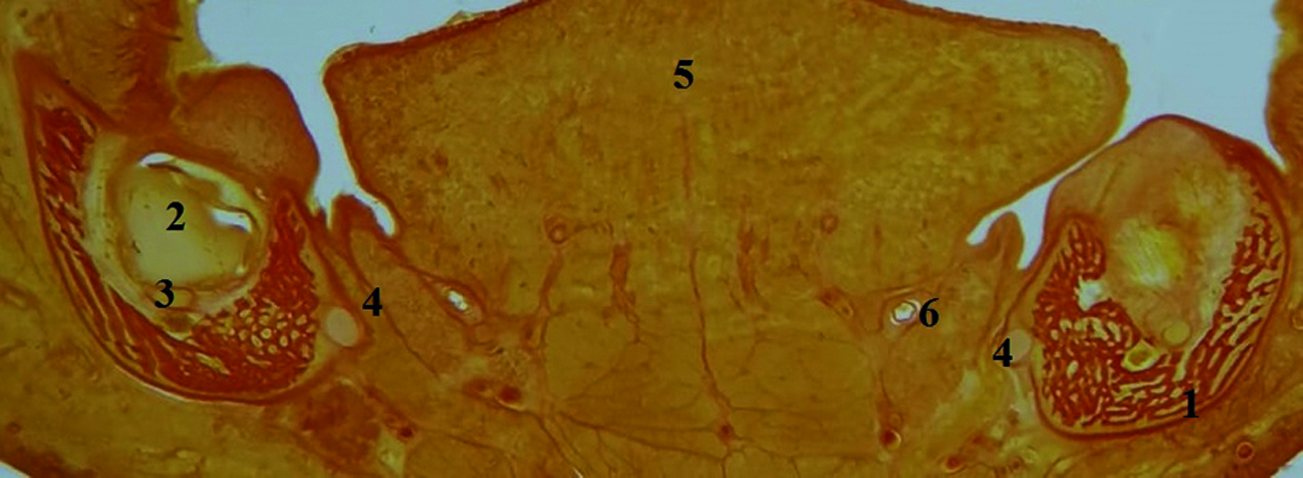

На сроке 19–23 недели вокруг зубных зачатков в мезенхиме челюстей появляются костные перекладины, формирующие стенки зубных альвеол, которые определяются макроскопически (рисунок 2) и на фронтальных гистотопограммах (рисунок 4).

Рисунок 4. Фрагмент фронтальной гистотопограммы нижней челюсти плода. 1 – стенка зубной альвеолы; 2 – зачаток молочного зуба; 3 – закладка постоянного зуба; 4 – нижний альвеолярный нерв; 5 – язык; 6 – подъязычная слюнная железа.

Примечание. Плод 19 нед.; жен.; окраска по Ван-Гизону. Фото под микроскопом MicroOptixMX 1150, ок. 10, об. 0,8.